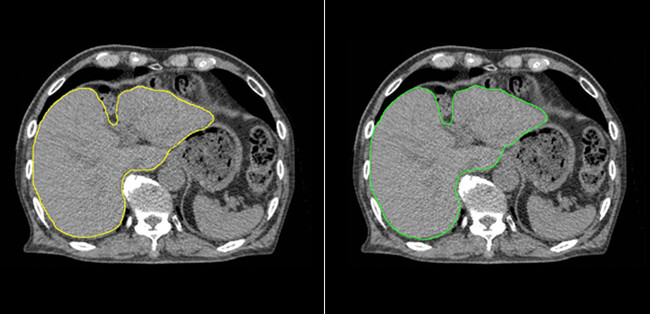

肝臓モデルを使用した例では、輪郭作成に要する時間は、従来の手作業のみでは30分以上要したものが、臨床利用ための人による修正時間も含め、Ai-Segによる自動輪郭作成及び必要に応じての軽微な修正作業を合わせて5分程度までに短縮することができました。図1に示すように医師とAi-Segが作成した輪郭を比較しても違いがわからないほどの水準にまで達しています。

[画像2: https://prtimes.jp/i/12662/412/resize/d12662-412-aaa905a64adb193d4743-0.png ]